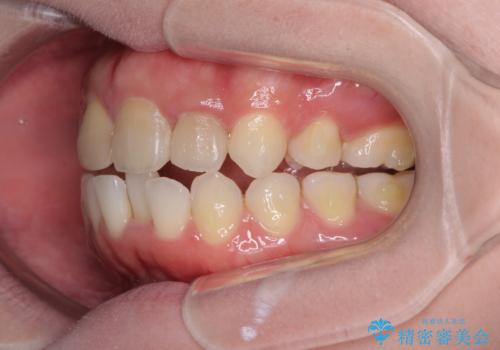

抜歯矯正の後戻り インビザラインによるオープンバイトの再矯正

- 以前矯正治療をされていましたが、後戻りが起きたことを気にして来院された患者様です。

上下前歯のオープンバイトを改善するため、インビザラインにて治療を行うこととしました。